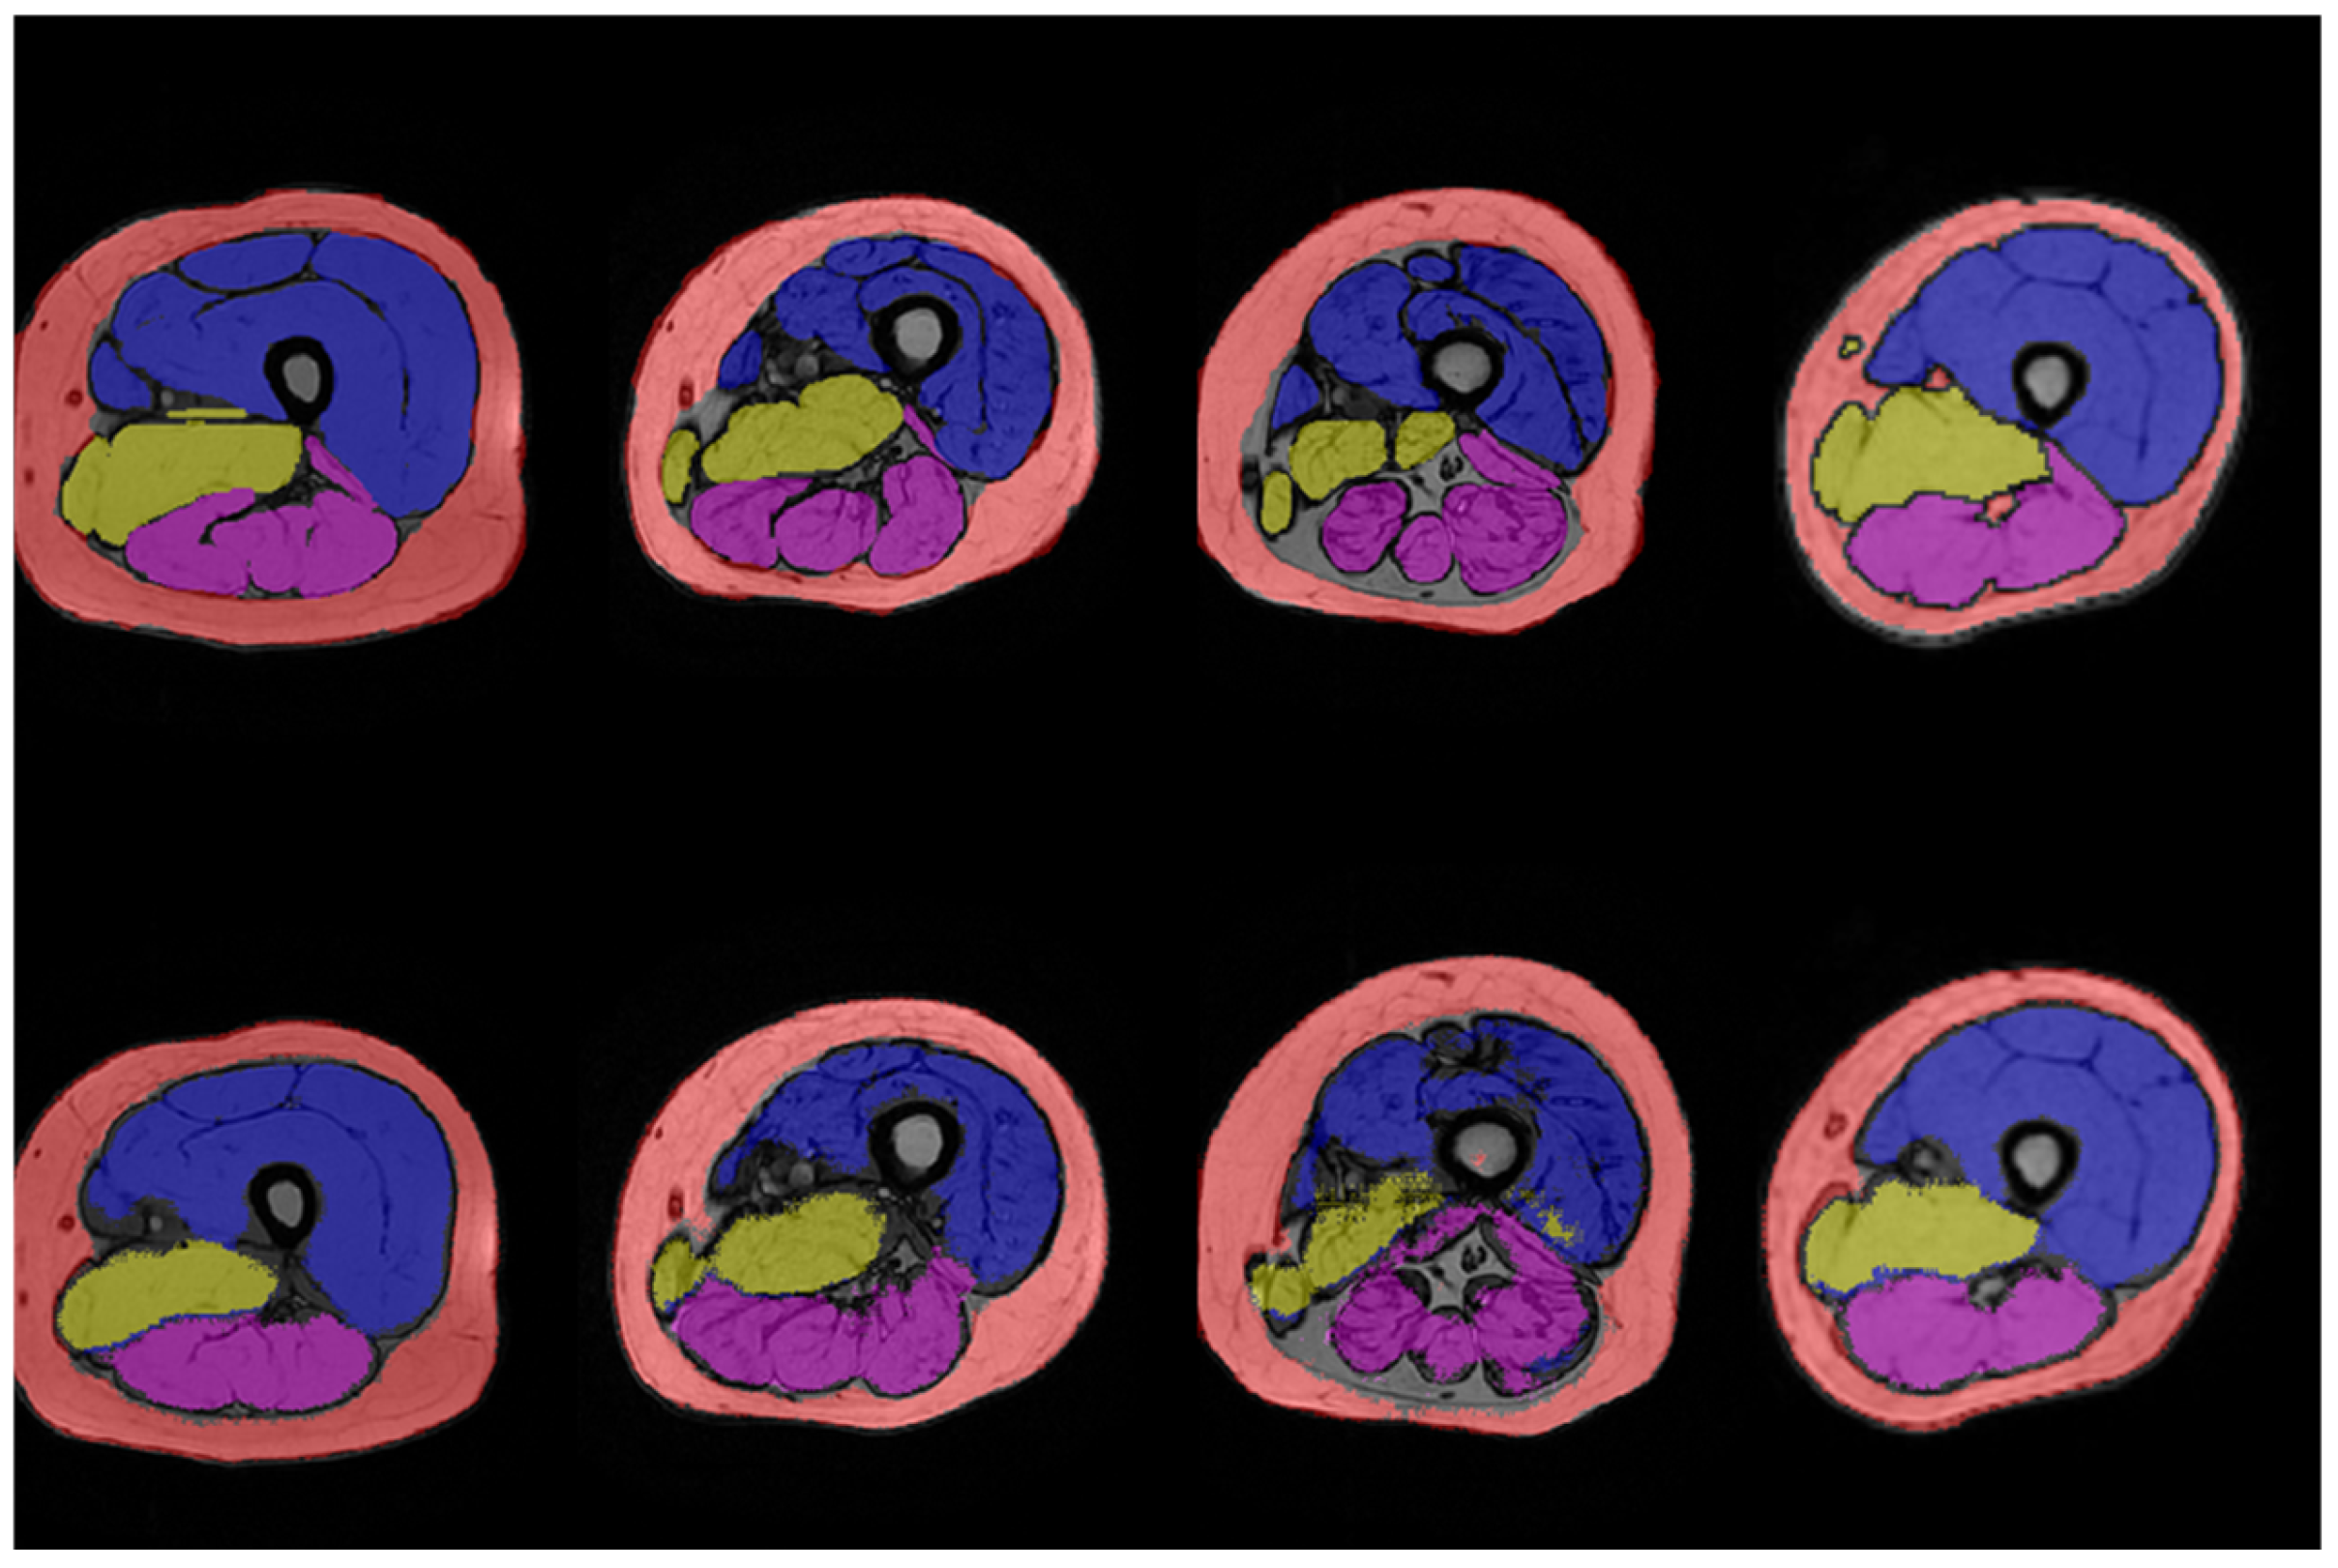

2.3. Manual Segmentation

2.5. Automatic Segmentation

3. Results